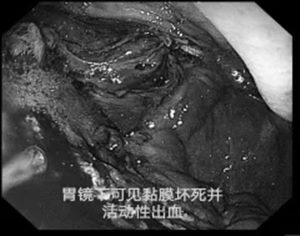

消化内科紧急行内镜探查,确定出血部位,提示存在胃黏膜坏死出血可能。彼时,患者血红蛋白一度下降至60g/L——仅及正常值的一半。虽积极大量输血,仍难以纠正贫血。

在取得家属充分同意后,患者被紧急转入胃肠·甲状腺外科,行急诊胃大部切除术。

术后,那条缓缓爬升的血红蛋白曲线,成为所有人最关注的风景。"血红蛋白站住了!"——这几个字,标志着出血被彻底控制,生命引擎重启成功。那一刻,所有参与救治的医护人员悬着的心,才终于安定下来。